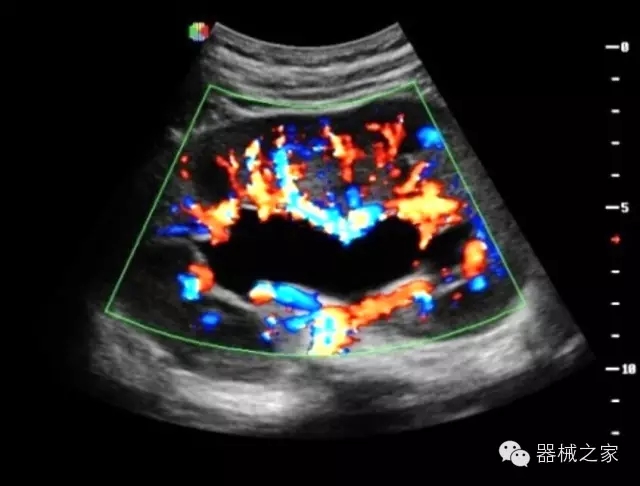

臨床圖片賞析

產(chǎn)品特點(diǎn)

優(yōu)異的成像技術(shù)

·亞陣元技術(shù):獨(dú)有的亞陣元技術(shù),對獨(dú)立晶片做二次切割,減少旁瓣偽像,增加臨床診斷的準(zhǔn)確性;

·μ-Scan微米成像技術(shù):開立獨(dú)有的μ-Scan技術(shù),還原出真實(shí)細(xì)膩、層次對比優(yōu)異的二維圖像;

·倒相諧波成像技術(shù):倒相諧波技術(shù)在去除基波信號的基礎(chǔ)上獲取兩倍二次諧波信號,提高組織圖像的對比分辨力;

·智能微血流成像技術(shù):智能微血流捕捉技術(shù)可以提取出隱藏在背景噪聲中的弱血流信號,大大提高低速血流的敏感性;

全面的臨床解決方案

超聲科常規(guī)領(lǐng)域應(yīng)用

·移植S40高端臺式彩超高端平臺技術(shù),滿足超聲科腹部、淺表、婦產(chǎn)科、心血管、肌骨等應(yīng)用,提供超聲科完美解決方案;

·實(shí)時(shí)的彈性成像技術(shù):提高了小器管(乳腺,甲狀腺、淺表軟組織腫瘤等)疾病鑒別診斷;

·IMT血管內(nèi)中膜自動(dòng)測量:為血管性疾病評估提供了有效的評估手段;

·心功能綜合指數(shù)(TEI指數(shù)):用于左、右心室整體心臟收縮舒張功能評估的測量方法;

·全方位可調(diào)M型:有利于更好的觀察心腔大小及室壁階段性運(yùn)動(dòng)的異常情況;

·組織多普勒成像(TDI):TDI可定量評價(jià)心肌運(yùn)動(dòng),判斷是否有局部病變,還可評價(jià)早期的舒張功能;

·高效3D/4D成像技術(shù):高速的4D幀頻,豐富的3D成像模式,智能斷層切片功能;